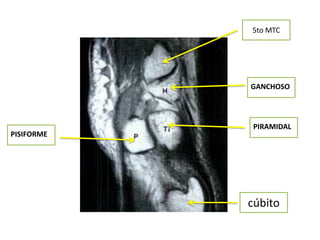

5to MTC

GANCHOSO

PIRAMIDAL

PISIFORME

cúbito